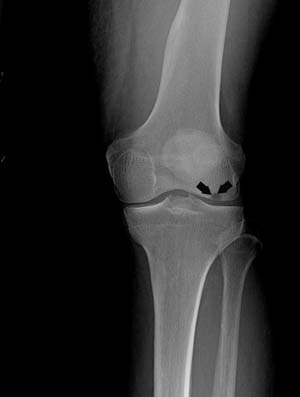

- Stage III: At this stage, the condition becomes clearly visible on X-rays and no other diagnostic tests are required. At this point, the bone itself begins to decay and cartilage covering the bones loosens from other segments of the leg. Surgical treatments are considered at this stage.

- Stage IV: In this stage, the articular cartilage is destroyed, joint space narrows, bone collapses, and bone spurs form. The only treatment at this point is joint replacement surgery.